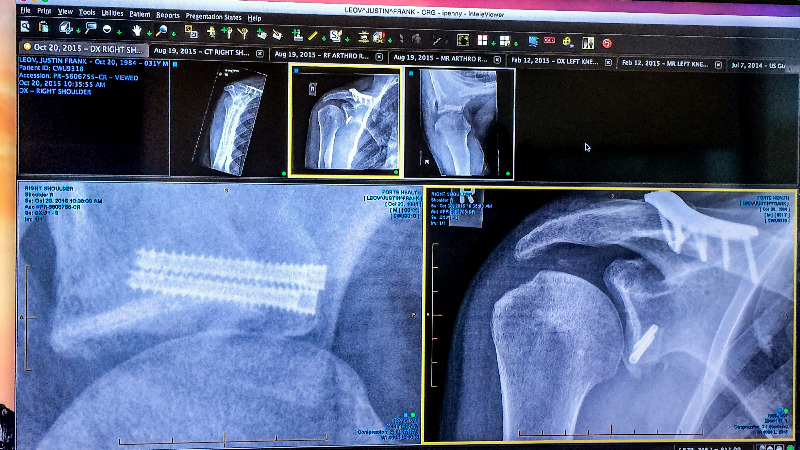

The silver lining is, I went back to New Zealand and got organized with a top surgeon who I have used previously. Fortunately he was able to fit my surgery in straight away, this may have been helped by the fact he is mad keen on Mountain biking. I had what is called a Laterjet procedure, which is in Simple terms, moving a small piece of bone in the shoulder and then re attaching it with two screws to a new location. The idea is that following the surgery the shoulder is reduced from the risk of future dislocations due to the bone in its new place. Although it is an open surgery, this should be a more robust solution for the long term and allow me to take a fall on it without any problems.